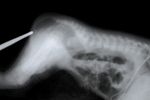

묘안 증후군은 환자마다 매우 다양한 증상을 나타낼 수 있다. 대표적인 특징 중 하나는 눈의 홍채 일부가 없는 홍채 결손으로, 이 모습이 고양이 눈과 비슷하다고 하여 "고양이 눈 증후군"이라는 별칭이 붙었다. 하지만 문헌에 보고된 환자 중 절반 이상은 이러한 특징적인 눈의 이상을 보이지 않는다.[6]

- 한쪽 또는 양쪽 홍채 결손 (눈의 색깔 부분 조직 부재)